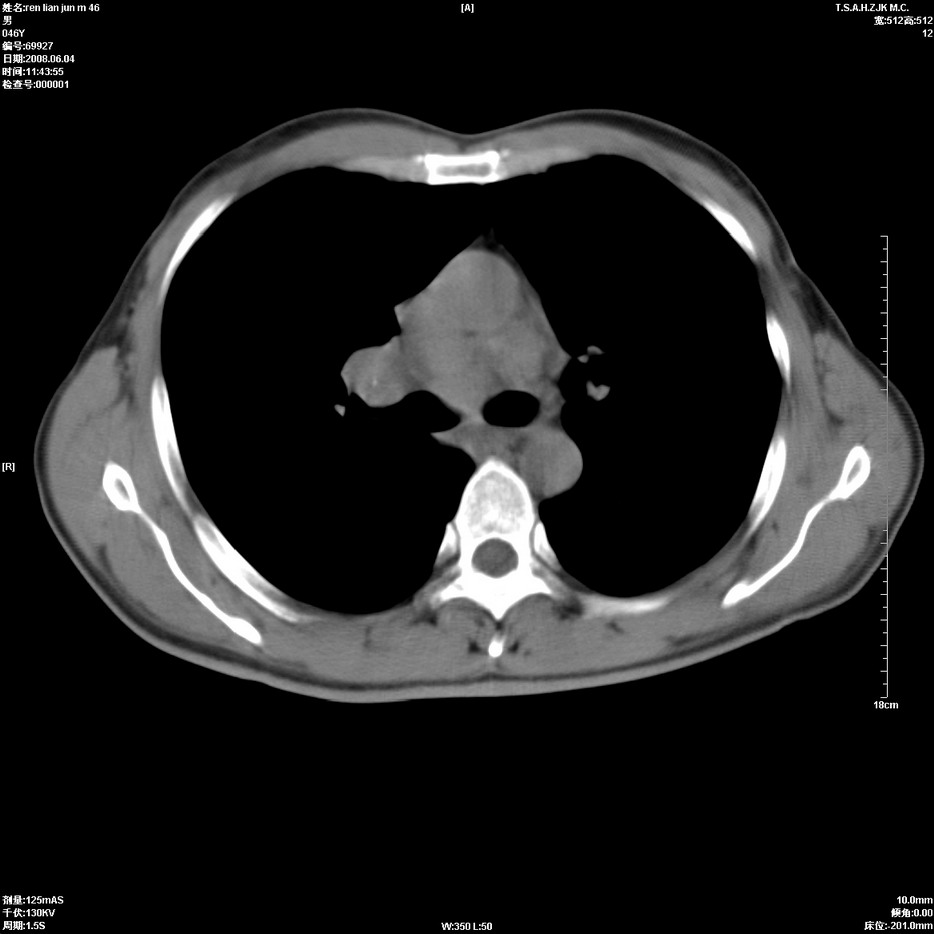

以下是引用qiu999在2008-6-5 17:14:00的发言:[br]考虑右肺中心型肺癌.颅内应做增强检查.

以下是引用形影不离在2008-6-5 19:18:00的发言:[br]右肺中心型肺癌并纵隔及左侧腋窝淋巴结转移,颅内应做增强检查。

以下是引用杀毒软件在2008-6-5 18:33:00的发言:[br]支持考虑右肺中心型肺癌,颅内病变是不是转移,不好说